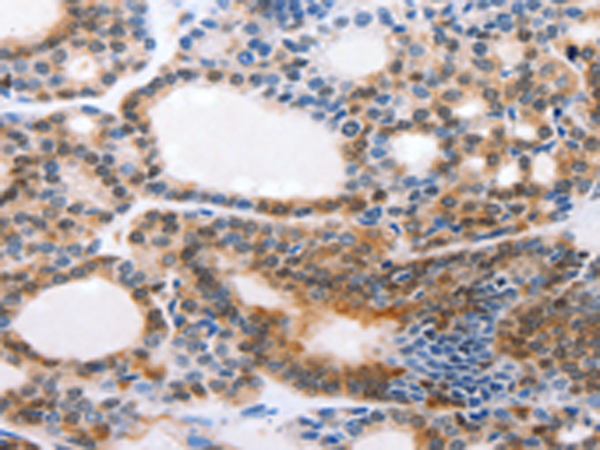

分类: 科研抗体货号: P03900别名: EPH, EPHT, EPHT1应用: IHC反应种属: Human, Mouse